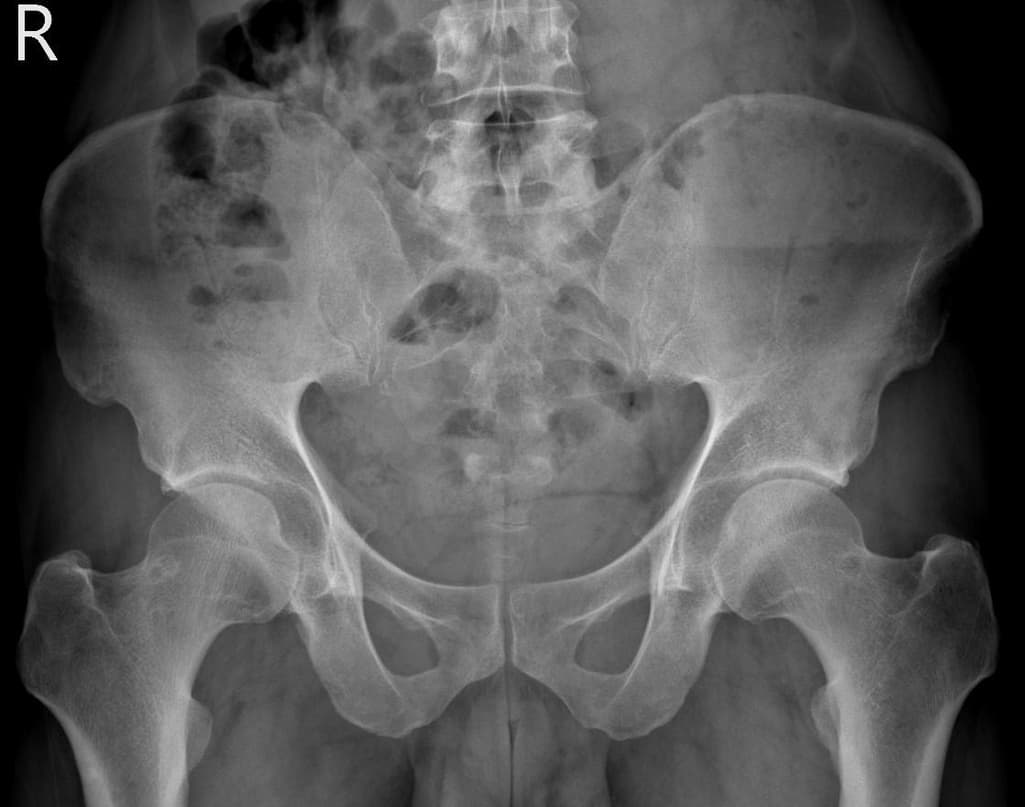

엑스레이 검사를 통해서는 현실적으로 뼈 위주의 평가만 가능하며 정밀하고 자세하게 평가를 내리는 것은 어렵습니다. 올리신 엑스레이 사진들에는 특별히 문제가 있다고 볼만한 소견이 크게 있어보이거나 하지는 않습니다.

올려주신 사진에서 크게 특이사항이 보이는 것으로생각되지는 않습니다.

고관절의 구조적인 이상보다는 주변 근육이나 신체기능, 근골격계질환등의 문제로 인해서 통증이 지속될 수 있으므로, 통증이 오래 지속된다면 전문적인 치료를 고려해보시면 좋겠습니다.